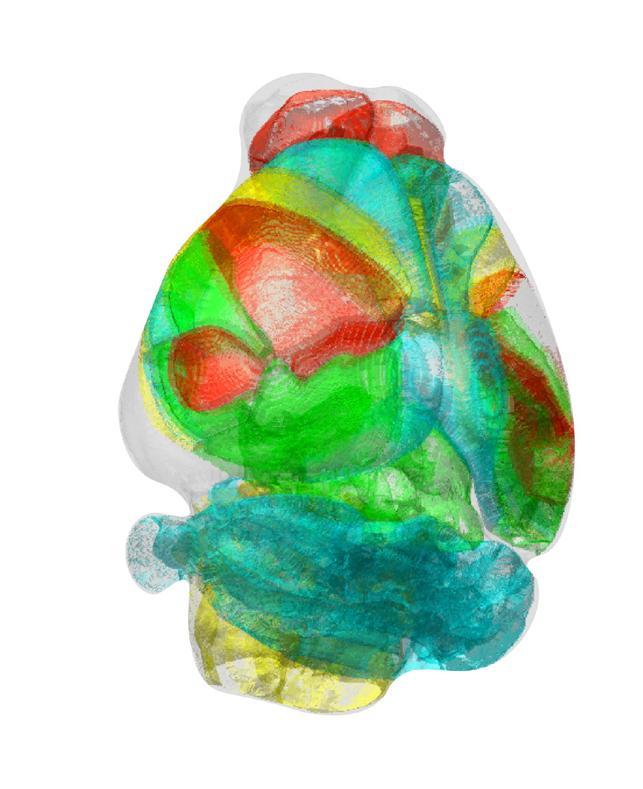

Automated 3D brain imaging data analysis technology offers more reliable and standardized analysis of the spatial organization of complex neural circuits.-

Credit: Professor Se-Bum Paik, KAIST

KAIST researchers developed a new algorithm for brain imaging data analysis that enables the precise and quantitative mapping of complex neural circuits onto a standardized 3-D reference atlas.

To address these issues, a KAIST research team led by Professor Se-Bum Paik from the Department of Bio and Brain Engineering developed new brain imaging data analysis software named ‘AMaSiNe (Automated 3-D Mapping of Single Neurons)’, and introduced the algorithm in the May 26 issue of Cell Reports.

AMaSiNe automatically detects the positions of single neurons from multiple brain images, and accurately maps all the data onto a common standard 3-D reference space. The algorithm allows the direct comparison of brain data from different animals by automatically matching similar features from the images, and computing the image similarity score.

This feature-based quantitative image-to-image comparison technology improves the accuracy, consistency, and reliability of analysis results using only a small number of brain slice image samples, and helps standardize brain imaging data analyses.

The two co-lead authors of this study, Jun Ho Song and Woochul Choi, exploited these benefits of AMaSiNe to investigate the topographic organization of neurons that project to the primary visual area (VISp) in various ROIs, such as the dorsal lateral geniculate nucleus (LGd), which could hardly be addressed without proper calibration and standardization of the brain slice image samples.

In collaboration with Professor Seung-Hee Lee’s group of the Department of Biological Science, the researchers successfully observed the 3-D topographic neural projections to the VISp from LGd, and also demonstrated that these projections could not be observed when the slicing angle was not properly corrected by AMaSiNe. The results suggest that the precise correction of a slicing angle is essential for the investigation of complex and important brain structures.